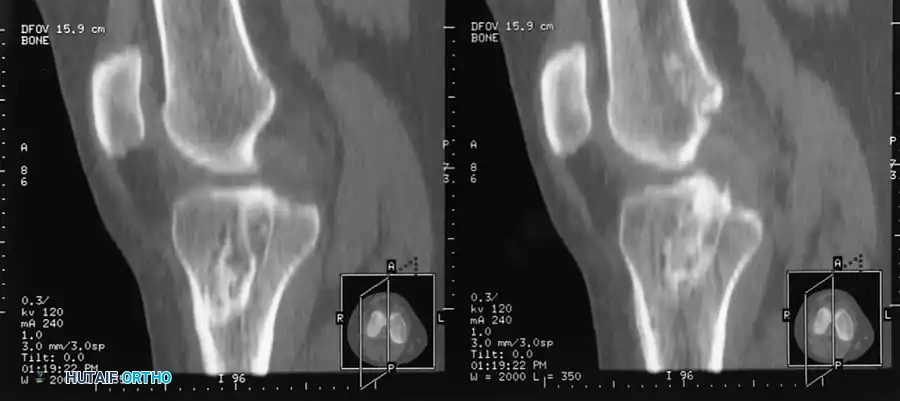

However, Computed Tomography (CT) is the gold standard for evaluating bone tunnel anatomy in the revision setting.

FIGURE 45-127: High-resolution CT scan with multiplanar reconstruction used to determine the exact location, trajectory, and size of existing bone tunnels before anterior cruciate ligament revision.

CT imaging allows the surgeon to accurately measure tunnel widening (osteolysis) and determine if the existing tunnels are anatomically placed. This dictates whether the old tunnels can be reused, if new tunnels must be drilled divergently, or if a staged bone-grafting procedure is mandatory.